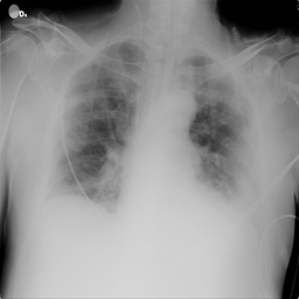

Data: COVID-19 Radiography Database from Kaggle

X-ray images of 4 lung conditions: Normal, COVID, lung opacity (LO), and viral pneumonia (VP)

Each of size 299 by 299 pixels having 10192, 3616, 6012, and 1345 images respectively.